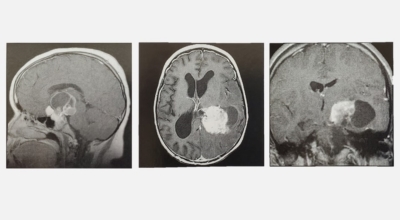

뇌종양이 악성인 경우, 빨리 자라는 특성이 있기 때문에 수술적으로 절제가 필요할 수 있습니다. 하지만 수술로 종양이 완벽하게 제거가 어려운 경우, 수술 후에 방사선 치료와 항암치료를 추가적으로 시행되어요. 요즘 들어서 뇌조직의 훼손을 최소화하고 수술 흉터가 거의 남지 않는 방법으로 하는 치료인 감마나이프 방사선 수술이 있답니다. 이 방사선 수술은 전신 마취와 피부 절개가 필요 없으며, 합병증이나 후유증이 적은 것으로 알려져 있답니다.

종양의 부위가 너무 커서 다른 방법을 활용하기 어렵거나 신경학적으로 생기는 증상이 너무 심하다고 판단이 될 경우에 활용할 수 있답니다. 하지만 다발성 병변으로 발생한 종양이거나 면역력이 많이 떨어져 있는 등 전신이 쇠약한 환자의 경우, 신중하게 생각해보아야 해요.